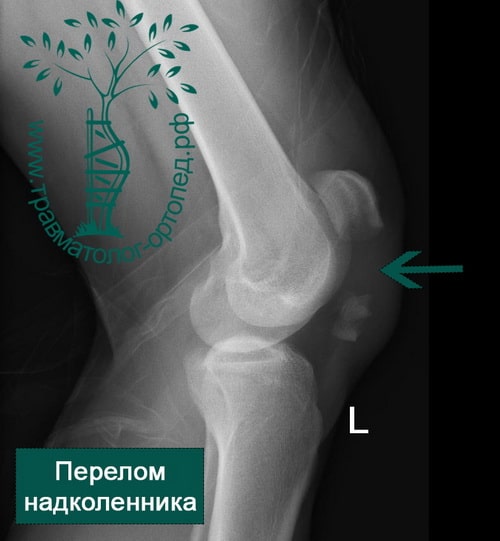

Как и при любой травме коленного сустава для постановки правильного диагноза выполняется рентгенография, на которой-то и можно увидеть перелом. Обычно рентгенографию выполняют в прямой и боковой проекциях, а для диагностики вертикальных переломов выполняют еще и осевую (аксиальную, или Merchant) проекцию.

Прямая (слева) и боковая (справа) проекции, на которых виден горизонтальный перелом надколенника со смещением отломков. Осевая проекция. Вертикальный перелом. Обратите внимание на возникшую в результате смещения ступеньку на скользящей поверхности надколенника.

Осевая проекция. Вертикальный перелом. Обратите внимание на возникшую в результате смещения ступеньку на скользящей поверхности надколенника.Иногда для более точного диагноза могут потребоваться компьютерная и/или магнитно-резонансная томография, но, в подавляющем большинстве случаев, достаточно рентгенографии.

Внешние признаки перелома надколенника имеют ряд характерных особенностей, тем не менее для уточнения диагноза обязательно проводятся рентгенологические исследования. Рентгенологически перелом надколенника особенно хорошо виден на боковом снимке, но в некоторых случаях необходим снимок и в прямой проекции (нога стоит прямо).

Рентгеновские снимки коленной поверхности и профиля будут выполняться систематически. Осевой вид шаровых шарниров в сгибании при 30 ° часто бывает невозможным из-за боли. Эта минимальная рентгенографическая оценка позволяет подтвердить диагноз, указать тип перелома и искать связанные поражения в колене.

Рисунок 7: Перерыв в разрушении. Рисунок 8: Поперечный перелом; профильная рентгенография. Сканер имеет мало пользы; он может дать возможность указать суставное смещение. Трехмерные реконструкции интересны в случае сложных измельченных трещин. Артроскопии нет места для диагностики.

Для подтверждения диагноза необходимо выполнить рентгеновские снимки в двух проекциях, иногда требуется выполнение аксиальной проекции, особенно при вертикальных переломах. Обычно, перелом надколенника хорошо виден на рентгеновских снимках.

На рентгенограмме показан перелом тела надколенника без смещения.

На рентгенограмме продемонстрирован перелом нижнего полюса надколенника.

Перелом надколенника слева со смещением отломков. Необходима операция.

Краевой перелом надколенника, хорошо видимый на аксиальной рентгенограмме.